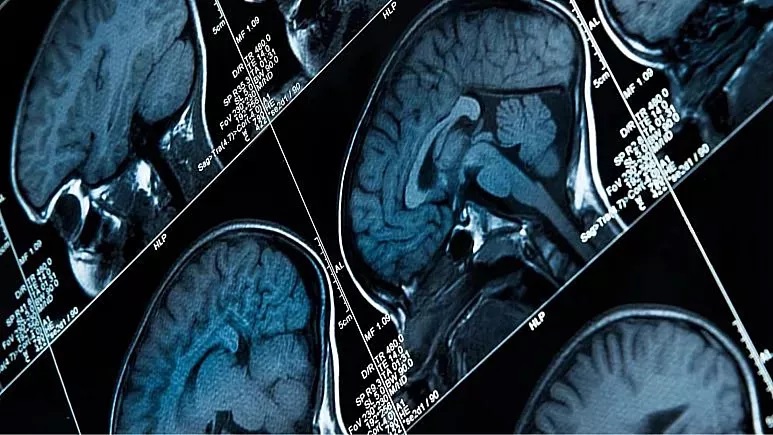

رمزگشایی سیگنال‌های مغزی برای احساس درد توسط محققان برای اولین بار

برای مدتهاست که محققان به دنبال درک چگونگی ایجاد سیگنال‌های درد در مغز هستند، با این حال تاکنون نتوانسته بودند آن را از نزدیک مشاهده کنند و حالا عده‌ای از دانشمندان موفق شده‌اند با استفاده از تکنیک یادگیری ماشینی برای اولین بار سیگنال‌های مغزی برای درد را ثبت کنند.

به گزارش سیتنا به نقل از یورونیوز، دانشمندان منطقه‌ای از مغز را شناسایی کرده‌اند که می‌گویند با درد مزمن مرتبط است. امری که امید به یافتن درمان‌های جدید برای اعتیاد به مسکن‌های قوی را افزایش داده است.

محققان با کاشت الکترود در داخل مغز افرادی که دارای اختلالات درد مزمن ناشی از سکته مغزی یا قطع عضو بودند، فعالیت‌های عصبی و داده‌های مربوط به درد را در طی ماه‌ها زیر نظر گرفتند. سپس با استفاده از مدل‌های یادگیری ماشینی، موفق شدند شدت درد ناشی از فعالیت عصبی را پیش‌بینی کنند.

محققان تا پیش از این داده‌های مربوط به درد مزمن را از طریق خوداظهاری بیماران و با استفاده از پرسشنامه‌هایی درباره شدت و تأثیر عاطفی درد جمع‌آوری می‌کردند. روش جدید اما مستقیما تغییرات حاصل شده از درد را در فعالیت‌های مغزی دو قشر سینگولیت قدامی (ACC) و اوربیتوفرونتال (OFC) ردیابی می‌کند.

دانشمندان از طریق جراحی الکترودهایی را در این دو بخش مغز بیماران کاشتند و فعالیت این دو ناحیه را زیر نظر گرفتند. سپس از تحلیل یادگیری ماشینی برای پیش‌بینی وضعیت درد مزمن شرکت‌کنندگان استفاده کردند.